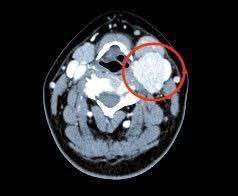

Самое сложное в операции то, что рядом находятся сосуды, питающие головной мозг. Малейшая неточность и человек может остаться инвалидом. У хирургов всё получилось — на контрольном приёме рецидивов у больной не было.